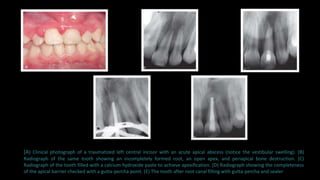

(A) Clinical photograph of a traumatized left central incisor with an acute apical abscess (notice the vestibular swelling). (B)

Radiograph of the same tooth showing an incompletely formed root, an open apex, and periapical bone destruction. (C)

Radiograph of the tooth filled with a calcium hydroxide paste to achieve apexification. (D) Radiograph showing the completeness

of the apical barrier checked with a gutta-percha point. (E) The tooth after root canal filling with gutta-percha and sealer